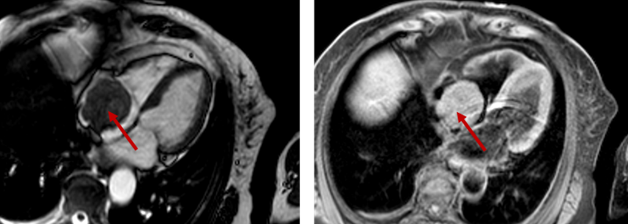

Zur Abklärung einer Herzmuskelentzündung werden verschiedene CMR-Sequenzen angewandt, um Inflammation im Herzmuskel darzustellen. Ferner kann mit CMR die Differenzierung zwischen den verschiedenen Kardiomyopathien oder Herztumoren erfolgen. Durch Verwendung neuer Mapping-Verfahren kann hoch-sensitiv eine Schädigung des Myokards oder eine Vergrößerung des Extrazellulärraumes erkannt werden.

Diagnostik der Herzmuskelentzündung

Diagnostik von Herztumoren